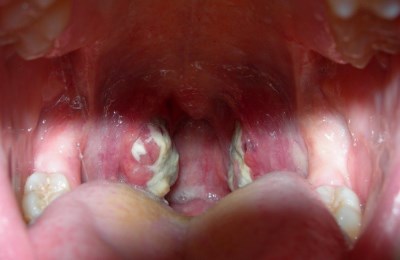

Ниже предоставляется фото больного ангиной горла, как видим, здесь присутствуют множество, противоположных симптомам здорового горла, признаков.

Врачи отмечают, что при ангине горло имеет характерные изменения, которые помогают в диагностике заболевания. В первую очередь, наблюдается покраснение и отек слизистой оболочки глотки. Миндалины, расположенные по обе стороны от горла, могут увеличиваться в размерах и покрываться белыми или желтоватыми налетами, что свидетельствует о наличии гнойного воспаления. В некоторых случаях отмечается наличие язвочек на миндалинах. Также пациенты часто жалуются на боль при глотании, что связано с воспалением тканей. Важно отметить, что при вирусной ангине изменения могут быть менее выраженными, чем при бактериальной. Врачам важно учитывать эти визуальные признаки для правильной диагностики и назначения адекватного лечения.

Горло при ангине приобретает ярко выраженный красный цвет с припухлыми миндалинами, также у некоторых возникают белые комочки с неприятным запахом.

При ангине горло выглядит воспалённым и отёчным. Люди часто описывают его как ярко-красное, с заметными белыми или желтоватыми налётами на миндалинах. Эти налёты могут быть признаком бактериальной инфекции, такой как стрептококк. Пациенты также отмечают, что горло болит при глотании, и это ощущение может сопровождаться сухостью и дискомфортом. В некоторых случаях наблюдается увеличение лимфатических узлов на шее, что свидетельствует о реакции организма на инфекцию. Многие отмечают, что при ангине голос становится хриплым или даже пропадает. Важно помнить, что при таких симптомах стоит обратиться к врачу для диагностики и назначения лечения.